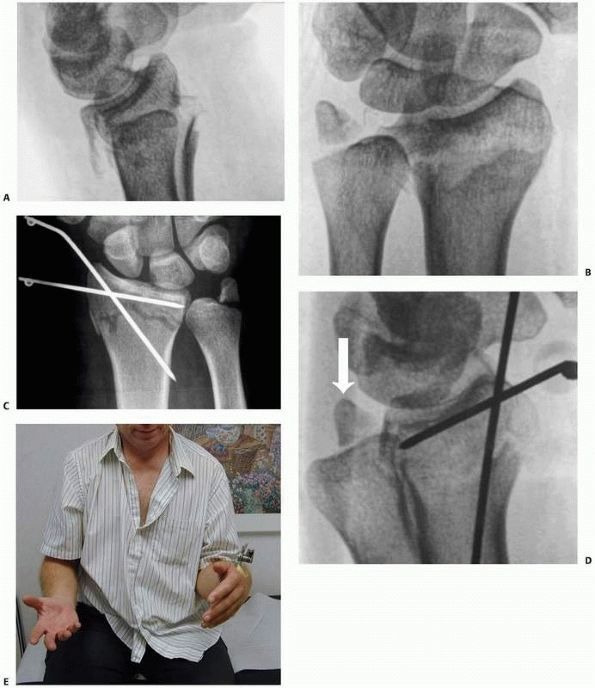

![]() |

FIGURE 30-22 A.

A fluoroscopic view of the distal pins for a nonbridging external fixator. The fracture is unreduced and the pins have been inserted parallel to the radiocarpal joint, between the fracture and the joint and engaging the volar cortex. B. The fracture has been reduced into palmar tilt using the pins as a “joystick.” Note the defect in the dorsal cortex from dorsal comminution. |

|

FIGURE 30-23 A. A three-part distal intra-articular fracture. B. Placement of shanz pins in the distal fragments through the palmar cortex allowing control of palmar tilt. C.

Note that these distal pins control both the radial and the intermediate column separately and that these fragments are locked into the construct |